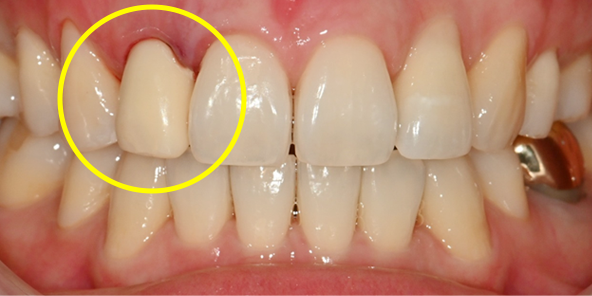

수술 당일 보철물 즉시 완성

2개월 후 잇몸의 형태가 바뀌거나 필요 시 2차 보철물(최종보철물)로 교체

2개월 후 잇몸의 형태가 바뀌거나

필요 시 2차 보철물(최종보철물)로 교체

임플란트 최종 결과

BEFORE/AFTER

AFTER